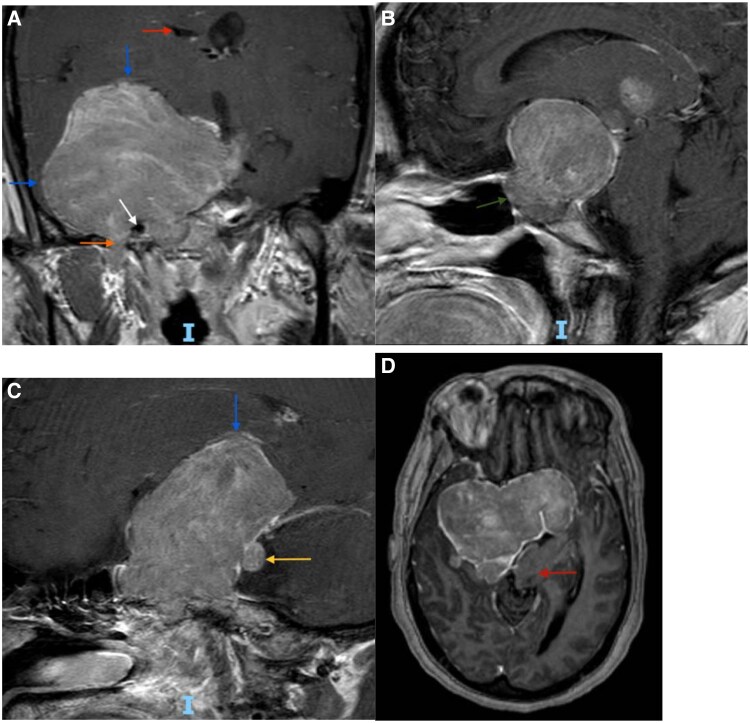

She experienced persistent menorrhagia, with bleeding nearly 20 days per month and frequent hospitalizations for symptomatic anemia. At age 46, she underwent a total abdominal hysterectomy with bilateral salpingo-oophorectomy (TAH-BSO). One year later, at age 47, surveillance MRI demonstrated residual tumor growth to 6.8 cm with new extension into the sphenoid sinus and foramen ovale (Fig. 1, panel C), prompting a third TSS. Despite treatment, and complicated by gaps in medical care, her tumor progressed to >8 cm with extension through the foramen ovale, posterior fossa invasion, and displacement of the brainstem (Fig. 2) with worsening vision loss, seizures, and auditory hallucinations by age 51.

Figure 2.

Magnetic resonance imaging brain (coronal, sagittal, and axial views) at age 51, taken during the patient's most recent clinical presentation, demonstrates tumor progression since the third TSS at age 47. (A) T1-weighted postcontrast image demonstrates interval growth of the tumor with significant mass effect on the right temporal lobe and the right inferior frontal lobe (blue arrows). There is posterior extension through the foramen ovale (orange arrow) and invasion of the right cavernous sinus with encasement of the right internal carotid artery (white arrow). There is also partial effacement of the right lateral ventricle (red arrow). (B) T1 postcontrast sagittal view image shows tumor extension into the sphenoidal sinus (green arrow). (C) T1 postcontrast saggital view image reveals displacement of the inferior frontal lobe (blue arrow) and invasion into the posterior fossa (yellow arrow). (D) Axial image shows leftward displacement of the brainstem (red arrow).

Abbreviation: TSS, transsphenoidal surgery.

Subsequent pituitary imaging 1 year later revealed progressive tumor enlargement to 6.8 cm (Fig. 2, panel C), necessitating a third TSS at the age of 47. Pathology showed dual LH and FSH expression, with a Ki-67 proliferation index of less than 1%. By the age of 51, the patient's tumor exceeded 8 cm, encasing the right internal carotid artery and invading the skull base (Fig. 2).

Surgical resection remains the standard of care for FGAs and often leads to hormonal normalization and symptom resolution. Although FGAs are typically slow-growing and responsive to surgery, a subset can behave aggressively, with rapid recurrence and local invasion. Wang et al reviewed several cases of FGAs in premenopausal women, observing that although most responded adequately to surgical resection, a subset required repeated surgeries, radiation, or additional medical therapy [2]. In this patient, serial imaging spanning more than a decade (Figs. 1 and 2) demonstrated progressive tumor growth to over 8 cm despite 3 surgical resections, with extensive local invasion and neurocognitive decline. Troullias et al's 2013 clinicopathological classification emphasizes the prognostic importance of tumor invasion, Ki-67 proliferation, and p53 expression in stratifying tumor behavior [6]. However, our patient's tumor demonstrated extensive growth and invasion despite a persistently low Ki-67 index (≤3%) and only focal p53 positivity. Such discordance between histological grading and clinical aggressiveness highlights the limitations in current prognostic markers, reinforcing the necessity of integrating clinical and imaging features in patient assessment. Similar discordance has been reported in other aggressive pituitary tumors with low Ki-67 and variable p53 expression [7, 8].